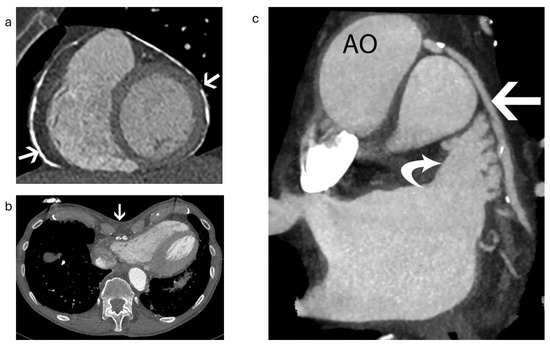

3.4. Pericardial Effusion and Device Erosion

3.5. Epicardial Devices